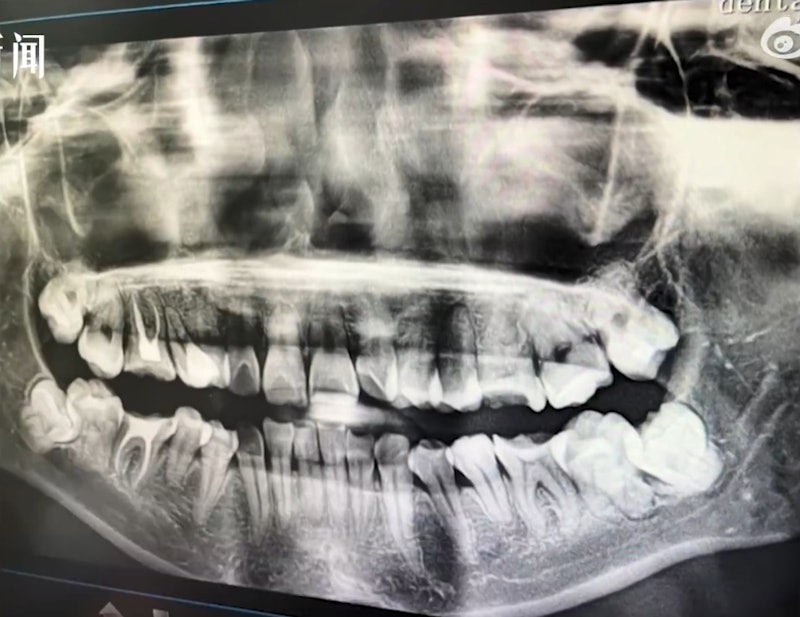

Ảnh chụp X-quang cho thấy bệnh nhân đã bị nhổ nhầm răng

Gia đình đã nhiều lần tìm đến bệnh viện để yêu cầu giải quyết nhưng không thành. Phải đến khi nạn nhân chụp phim tại một bệnh viện khác, sự thật mới được phơi bày.